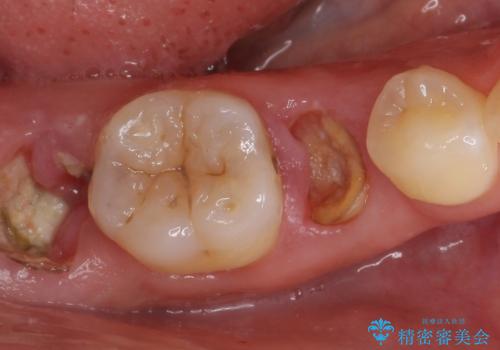

精査したところ、右下の奥歯2本(右下75)は大きなう蝕により歯冠が崩壊し保存不可能な状態でした。

プラークコントロール不良につき仮歯を精密に合わせても歯肉の腫脹を認めたため、工夫を凝らして精密な型取りを行うことで適合の良いクラウンを製作致しました。

クラウンの種類:ベレッツァクラウン